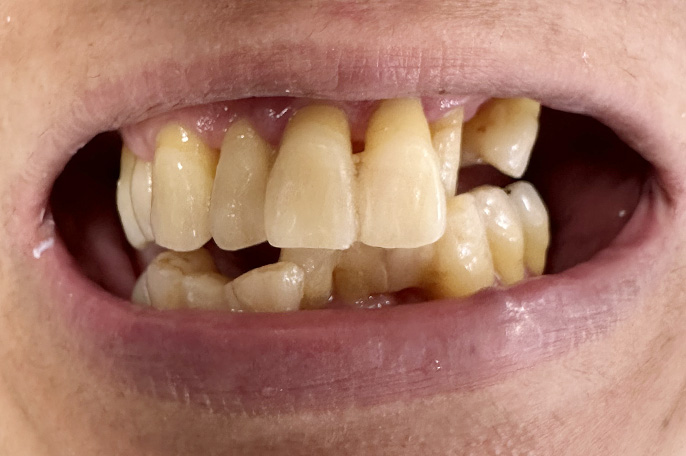

オールオン4 症例・48歳女性主訴:上下の歯を綺麗にしたい。

口の中がボロボロでマスクが外せないという患者様です。上下オールオン4にて治療しました。上下4本ずつインプラントが入っています。即日で綺麗な仮歯が入って満足していただけました。

| 治療期間 | 4ヶ月 |

|---|---|

| 治療費 | 4,400,000円(税込) ※施術代、インプラント、被せ物、CT全て込み |

| メリット | 即日で抜歯してインプラント治療と仮歯のセットまで行いますので歯がない期間がありません。従来のインプラント治療だと1年程度かかるケースですが、オールオン4を選択することによって治療期間が短縮できます。 |

| デメリット | 外科処置を伴います。 |

| 起こりうる症状 | 外科処置後の腫れ、痛みが出ることがあります。セラミックが破折することがあります。 |

術前

術後